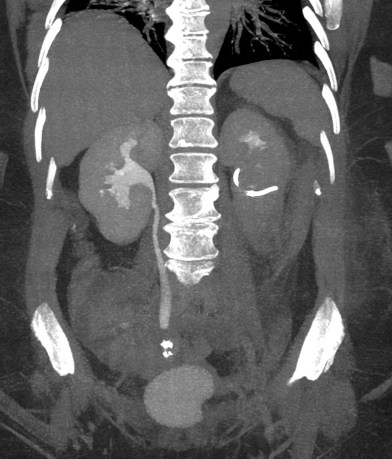

CASO CLÍNICO: Recopilatoción.

Paciente de 59 años con antecedentes personales de Cá de vejiga.

Se le realiza una Uro-Tc por seguimiento al año, aunque en esta ocasión el paciente refiere episodio de hematuria.

Tras el tratamiento de la recidiva y nefrostomía para la hidroureteronefrosis, vuelve acudir al hospital a los 9 meses por episodio de dolor en FD y malestar general. Se realiza una ecografía de urgencias.

Se realiza nueva TC bifásico abdominopélvio y Uro TC.

- Paciente con numerosas recidivas por Cá vejiga.

- Ha desarrollado un tumor metacrónico en pelvis renal derecha, también responsable de la hidroureteronefrosis.

- Mala evolución radiológica del proceso a expensas de metástasis pulmonares y hepáticas.